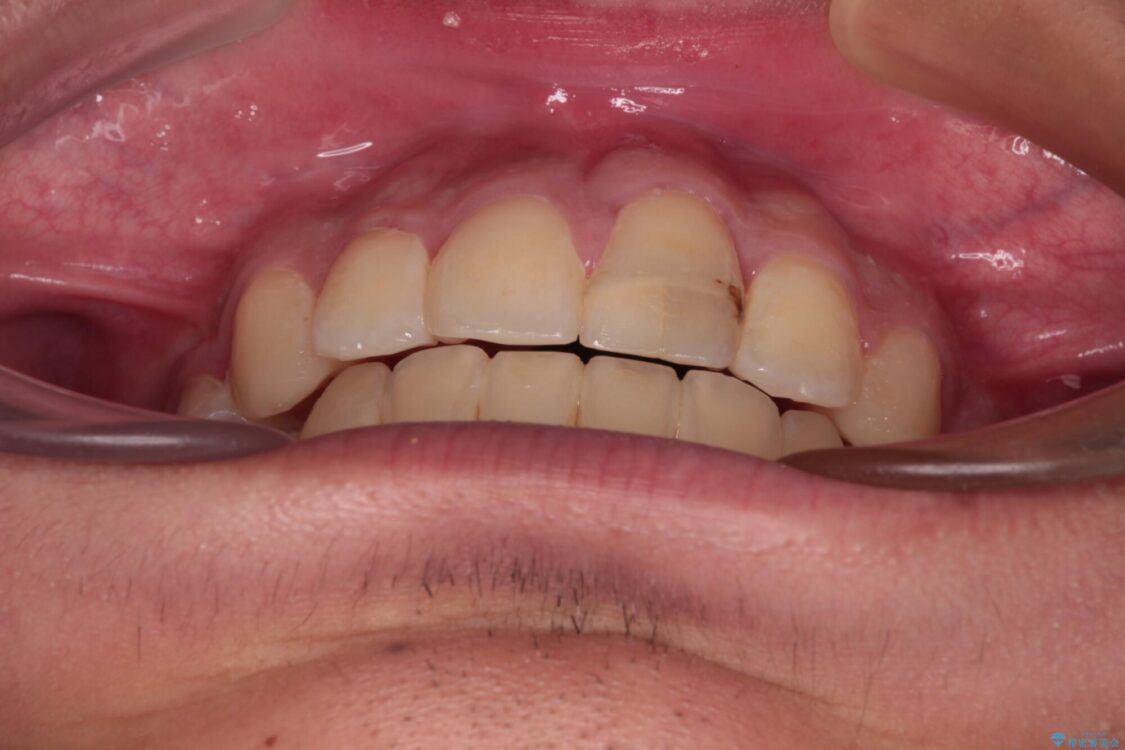

治療後

• 膨らんだ口元 ワイヤー装置での抜歯矯正 治療後画像

小学生の頃に上顎前歯をぶつけ、歯の一部が破損している状態であったので、歯根が歯槽骨と癒着して移動しない可能性がありましたが、無事に治療を終えることができました。

受験勉強と重なり、舌のトレーニングが十分に行えず、高校生としてはやや長期間の治療となりました。